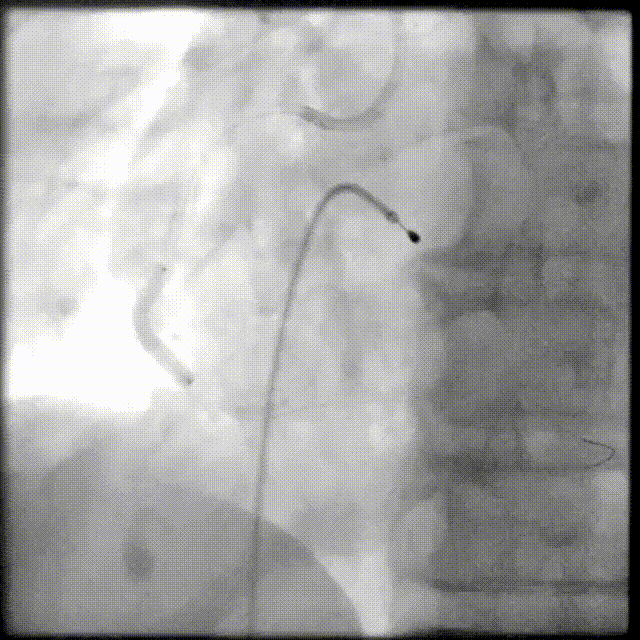

PCI过程-DES植入

由远及近依次送4.0X23mm、4.0X29mm、4.0X13mm DES至病变处串联释放。

PCI过程-支架后造影